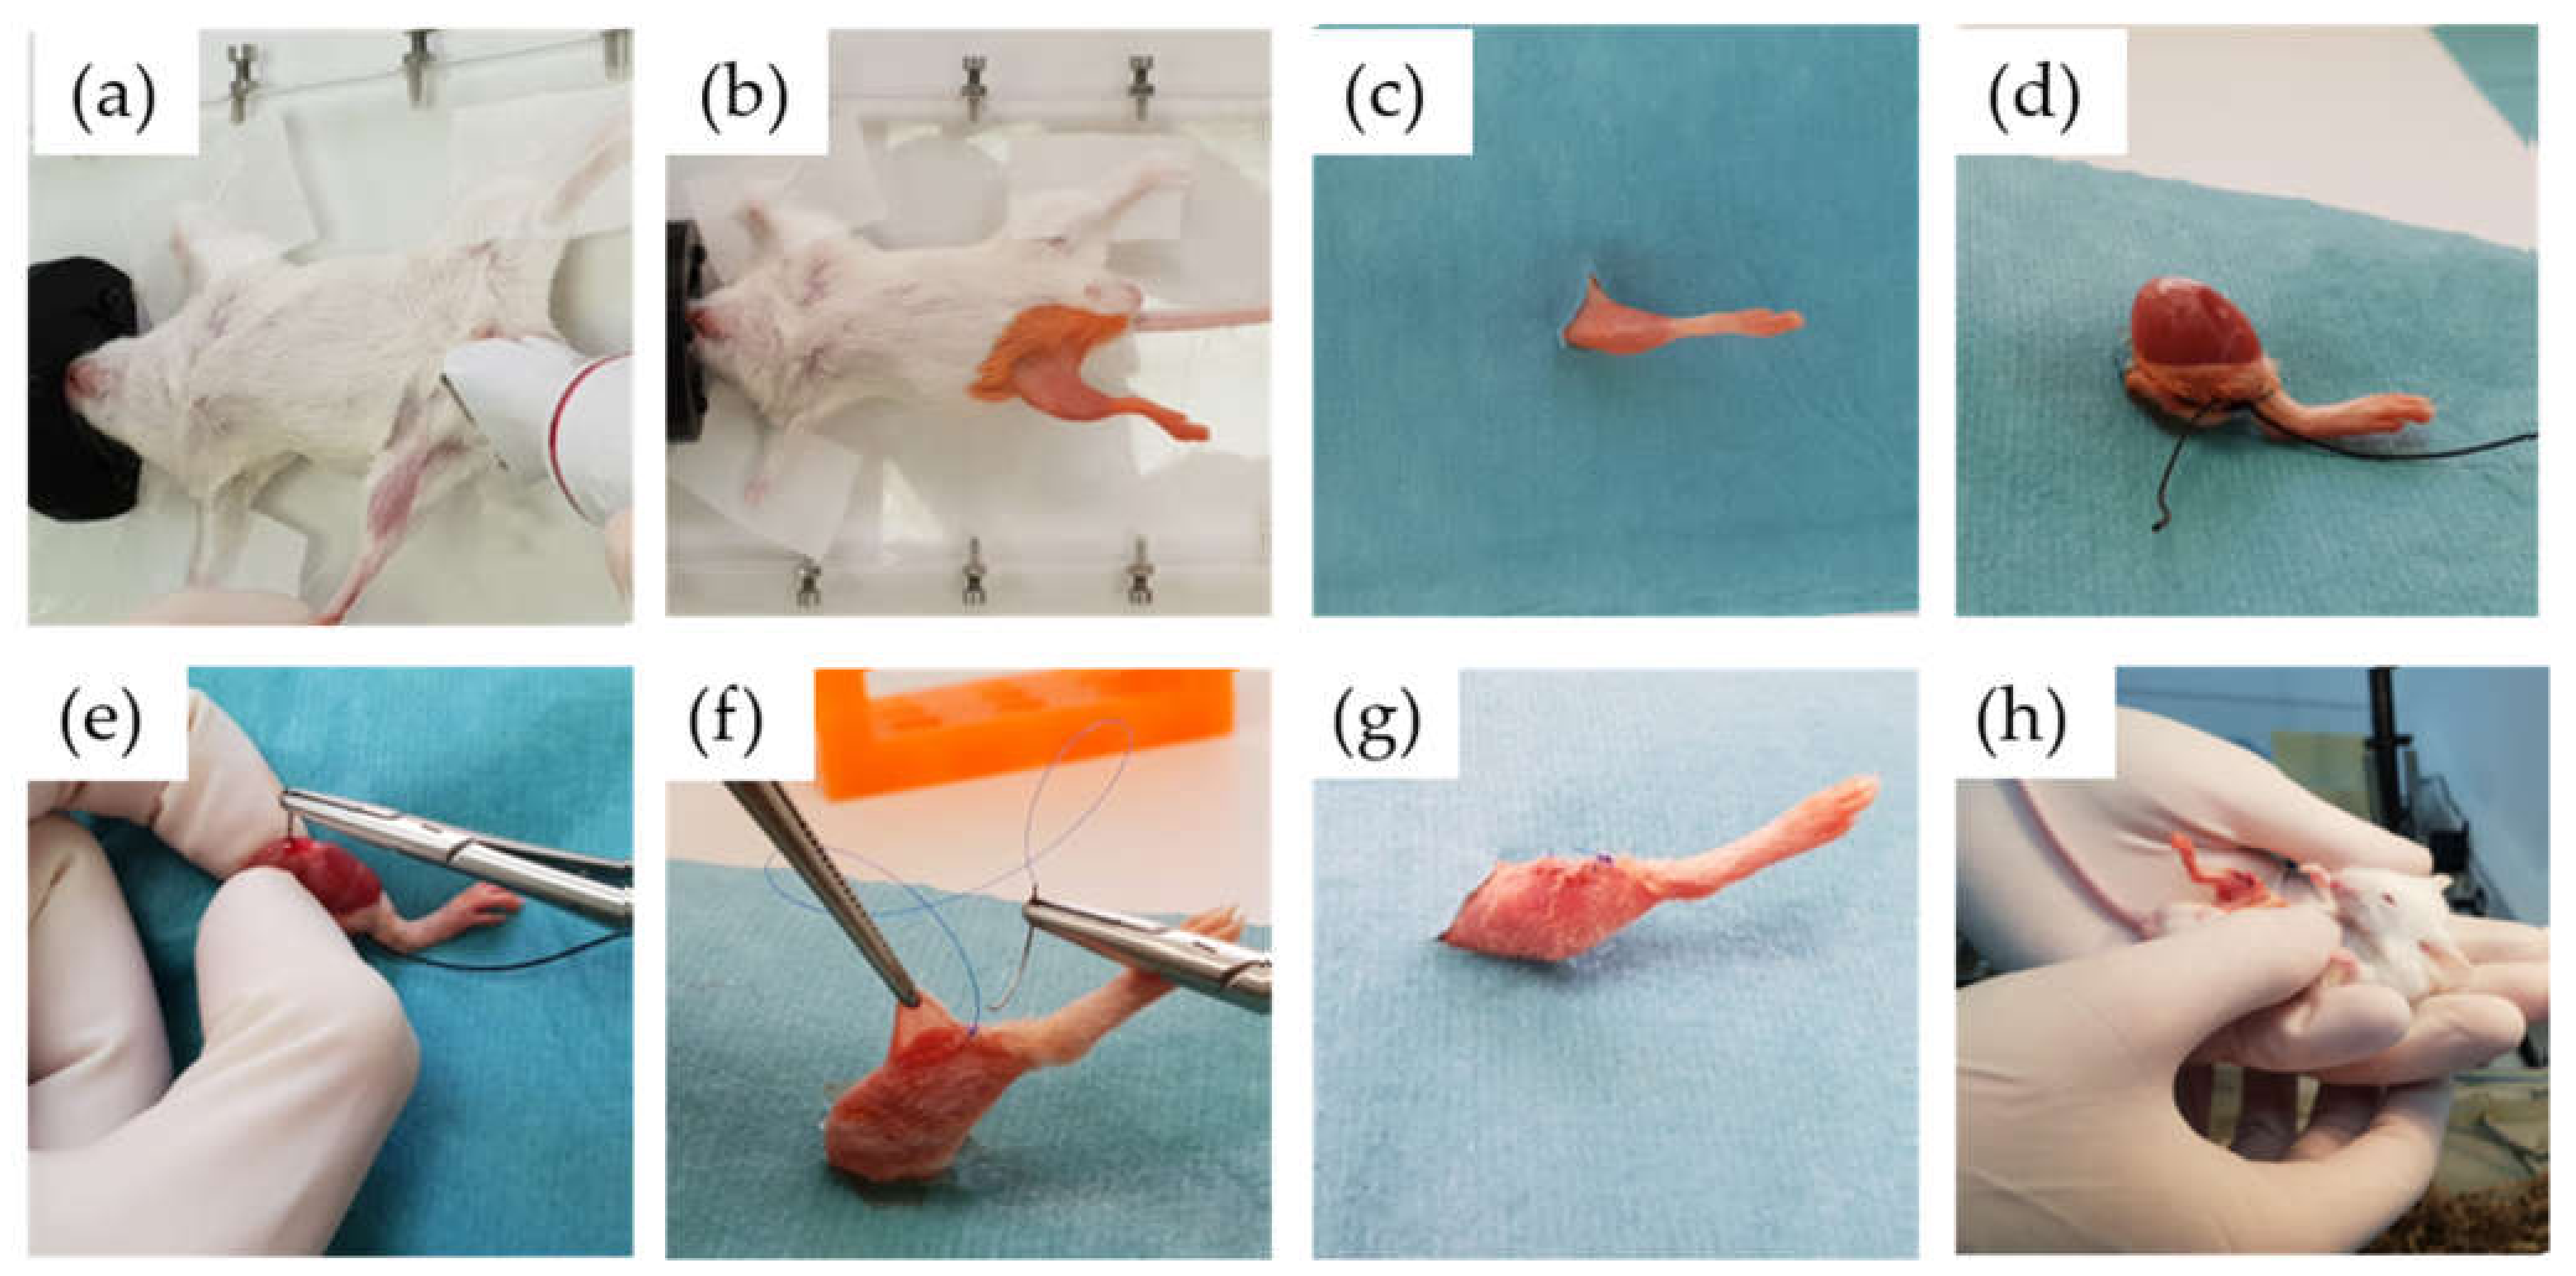

4.2. Animal Surgical Model and Monitoring